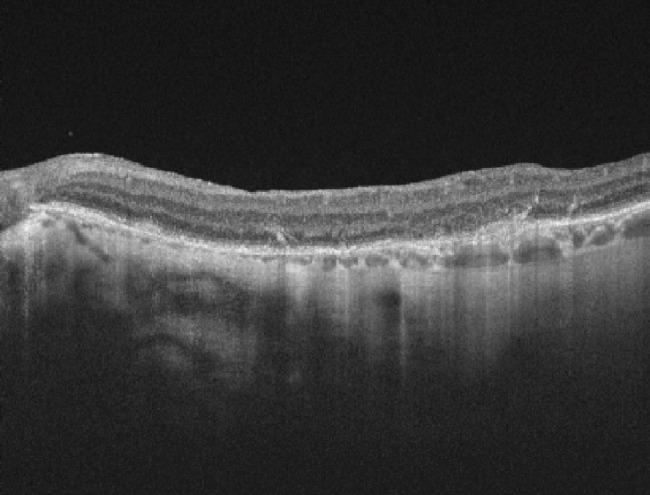

To describe the development of retinal pigment epithelium (RPE) atrophy after uncomplicated pars plana vitrectomy (PPV) with epiretinal membrane (ERM) and/or internal limiting membrane (ILM) peeling in 2 patients. : Case 1: A 79-years-old female with diagnosis of a full-thickness macular hole in her right eye (OD) with best corrected visual acuity (BCVA) of: 20/100 and left eye (OS): 20/70. After surgery she developed large RPE hyperplasia and presented hand movement that did not improve with pinhole. Case 2: A 69-years-old female patient who had ERM in her OS with BCVA of 20/30 in both eyes (OU). PPV was assisted with brilliant blue (BB) to better visualize the ILM. During follow-up visits we evidenced RPE atrophy in the zone where peeling was done. In the last control after 2-years, her visual acuity was 20/40 that did not improve with pinhole. There are three possible mechanisms to explain this complication: toxic damage, mechanical trauma during the membrane removal with forceps, or a combination of both. In our cases, a combination of them is probably the cause of the presence of RPE atrophy. Vitrectomy with membrane removal is successful in most cases with low rate of complications. Because RPE atrophy is infrequent, our suggestion is to continue performing this technique and if possible, it should be done without dye staining to minimize risks. ERM = epiretinal membrane, ILM = internal limiting membrane, MH = macular hole, RPE = Retinal pigment epithelium, OD = right eye, BCVA = Best corrected visual acuity, OS = left eye, OU = both eyes, IOL = intraocular lens, OCT = Optical coherence tomography, BB = Brilliant blue, TB = Trypan blue, ICG = indocyanine green.

描述 2 例单纯性孔源性视网膜脱离(PPV)伴内界膜(ILM)剥除术后无并发症的视网膜色素上皮(RPE)萎缩的发展。病例 1:一名 79 岁女性右眼(OD)全层黄斑裂孔,最佳矫正视力(BCVA):20/100,左眼(OS):20/70。手术后,她发生了较大的 RPE 增生,并出现手动视力,无法通过小孔改善。病例 2:一名 69 岁女性,OS 有 ERM,双眼 BCVA 为 20/30(OU)。PPV 采用亮蓝(BB)辅助,以更好地观察 ILM。随访时,我们在进行剥除的区域发现了 RPE 萎缩。最后一次随访 2 年后,她的视力为 20/40,无法通过小孔改善。有三种可能的机制可以解释这种并发症:毒性损伤、用镊子去除膜时的机械创伤,或两者的结合。在我们的病例中,两者的结合可能是 RPE 萎缩的原因。大多数情况下,膜切除玻璃体切除术是成功的,并发症发生率低。由于 RPE 萎缩并不常见,我们的建议是继续进行这种技术,如果可能的话,应在不染色的情况下进行,以降低风险。ERM = 视网膜内界膜,ILM = 内界膜,MH = 黄斑裂孔,RPE = 视网膜色素上皮,OD = 右眼,BCVA = 最佳矫正视力,OS = 左眼,OU = 双眼,IOL = 人工晶状体,OCT = 光学相干断层扫描,BB = 亮蓝,TB = 锥虫蓝,ICG = 吲哚青绿。